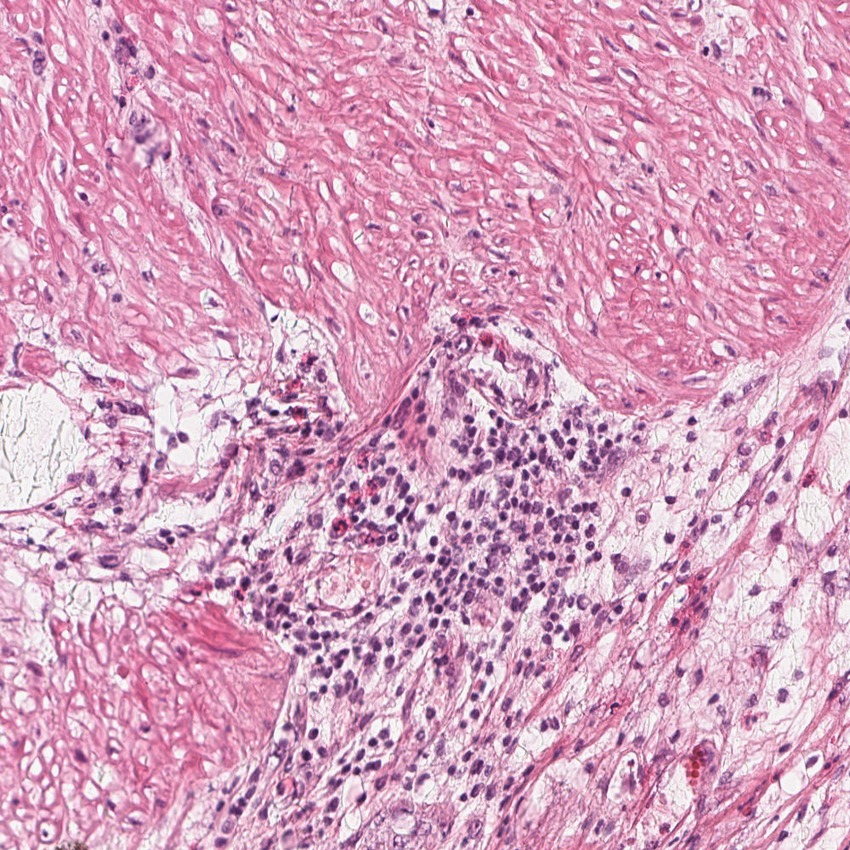

Smooth muscle cells:

80

Other cell types:

20